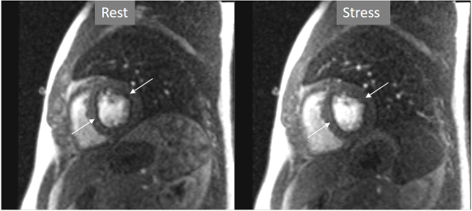

The aim of perfusion studies is the demonstration of a blunted increase—or a reduction—in regional MBF in response to a vasodilator stimulus which can be attributed to a flow-limiting coronary artery lesion. Rest perfusion studies alone are not useful in this sense, as basal MBF is kept within normal limits even in territories supplied by a severely stenosed vessel, and is only after a vasodilator agent has been given that the reduction in CFR can be evidenced [24]. In CMR studies, this situation is detected as a reduced increase in SI of the underperfused territories (Fig. 3).

Fig. 3.Induced perfusion defect. Subendocardial perfusion defect at the interventricular septum during stress (left panel, black arrow), not present at rest (middle panel), in a patient with significant coronary stenoses in the left anterior descending (LAD) artery (right panel, white arrows).